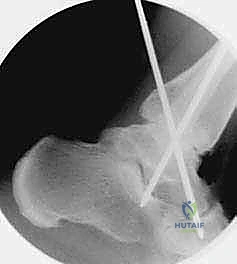

هو إحداث توازن مثالي بين الجراحة المفتوحة وجراحة المناظير. يقوم الأستاذ الدكتور محمد هطيف بإجراء الجراحة عبر شقين أو ثلاثة شقوق صغيرة جداً (لا تتجاوز 2-4 سم). من خلال هذه النوافذ الصغيرة، وباستخدام أدوات جراحية دقيقة ومخصصة، يتمكن من الرؤية المباشرة للمفصل، وإزالة الغضاريف التالفة بالكامل، وتجهيز العظام للدمج، ثم تثبيتها بالبراغي.

1. الحفاظ على التروية الدموية: عدم قطع الأنسجة المحيطة يحافظ على تدفق الدم الممتاز للعظام، وهو العامل الأهم لنجاح الاندماج العظمي.

- التصوير المقطعي المحوسب (CT Scan): إجراء بالغ الأهمية قبل الجراحة. يوفر صوراً ثلاثية الأبعاد للعظام، مما يساعد الدكتور هطيف في تقييم جودة العظم بدقة، تحديد حجم التكيسات العظمية، والتخطيط الهندسي الدقيق لزوايا إدخال البراغي الجراحية.